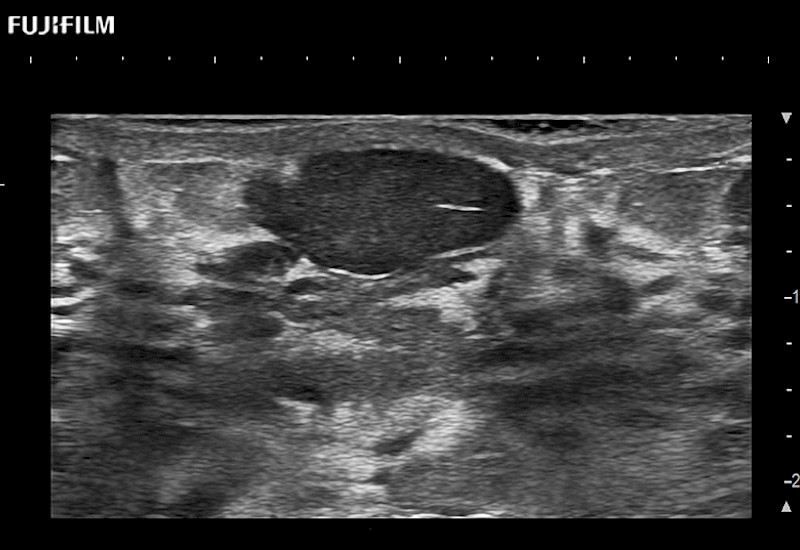

For precise surgical oncology ultrasound imaging, Fujifilm Healthcare offers premium level solutions that include:

Extraordinary high-resolution digital imaging

Our dedication to Surgical Oncology allows us to offer superior image quality, outstanding system reliability and intuitive use of cutting edge technology.

- Exceptional near and far-field resolution

- Instant feedback on tumor margin delineation

- Valuable information to guide tumor resections

- Exceptional near and far-field resolution

- Instant feedback on tumor margin delineation

- Exceptional near and far-field resolution

- Instant feedback on tumor margin delineation